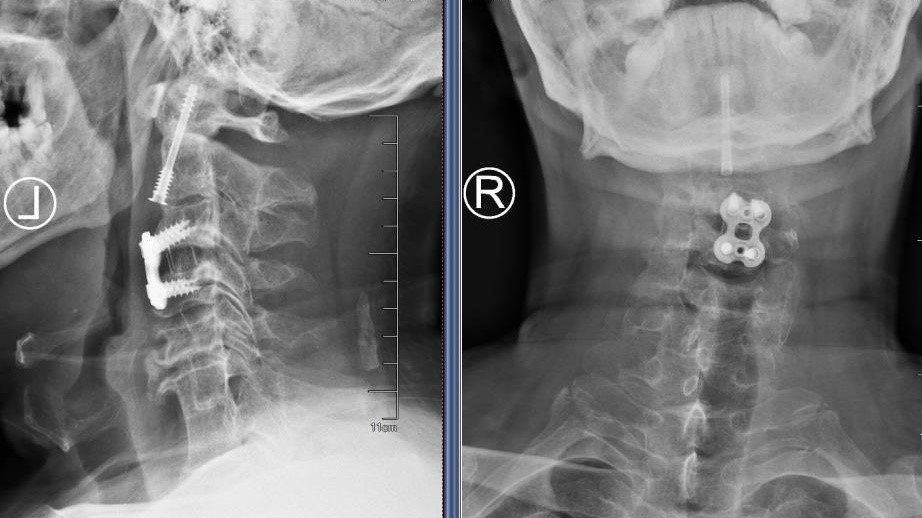

图3:骨科机器人

在麻醉手术科的严密监护下,刘义杰副主任医师首先熟练地完成了颈椎前路C3-4减压融合术(ACDF),成功解除了脊髓的压迫。然而,通过同一个仅3厘米的微小切口,精准地将螺钉植入游离且向后倾倒的齿状突具有极大的挑战性。关键时刻,骨科手术机器人发挥了“超级助手”的作用。团队利用机器人导航系统,对进钉点和角度进行了反复测算与调整,导针精准抵达目标。随后,由姜为民主任专利研发的一枚新型齿状突螺钉顺着通道顺利旋入,牢牢锁住了骨折端。整个过程出血量少,手术顺利完成。